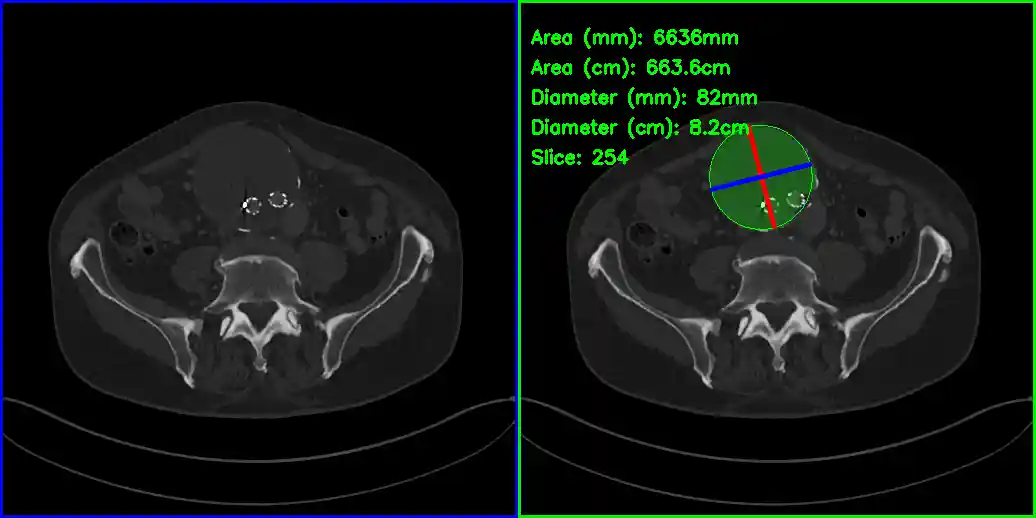

AAA Segmentation and Maximum Diameter Measurement

Example Output Image (slice with largest diameter)